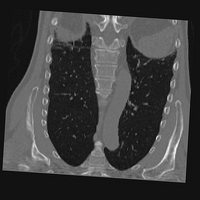

Exp. 3: Adult thorax data: To show the versatility of our approach we also apply it to adult thorax scans. For this experiment no organ specific training is performed but the whole volume is used. We evaluate reconstruction performance similar to Exp. 1 and Ti^^subscript𝑇𝑖\hat{T_{i}} prediction performance when ΩΩ\Omega is projected on an external plane, comparable to X-Ray examination using C-Arms. The latter provides insights about our method’s performance when applied to interventional settings in contrast to motion compensation problems. 60 healthy adult thorax scans were randomly selected, 51 scans used for ΩtrainsubscriptΩ𝑡𝑟𝑎𝑖𝑛\Omega_{train} and nine scans used for ΩvalidationsubscriptΩ𝑣𝑎𝑙𝑖𝑑𝑎𝑡𝑖𝑜𝑛\Omega_{validation}. Each scan is intensity normalised and resampled in a volume of 200×200×200200200200200\times 200\times 200 with spacing 1mm×1mm×1mm1𝑚𝑚1𝑚𝑚1𝑚𝑚1mm\times 1mm\times 1mm. Using the Fibonacci sampling method, 25 sampling plane of size 200×200200200200\times 200, evenly spaced between -50 and +50, were rotated over 500 normals. Training took approximately 20 hours for 60 epochs. Fig. 4c shows an example reconstruction result gaining 28dB PSNR with additional SVR. Ti^^subscript𝑇𝑖\hat{T_{i}} prediction takes approx. 20 ms/slice for this data.

Figure 4: (a): Comparison of a single slice from raw low-dose thorax CT data; (b): reconstruction based on SVRNet Ti^^subscript𝑇𝑖\hat{T_{i}} regression; (c): SVR initialized with SVRNet transformations after four iterations of SVR; (d): PSNR of (b) and (c) compared to (a). (e): shows a projection of an unseen pathological test CT volume as DRR and (e) shows a DRR at the location predicted by our method when presented with the image data in (e).

We use Siddon-Jacobs ray tracing [15] to generate Digitally Reconstructed Radiographs (DRRs) from the above described data. For training, we equally sample DRRs on equidistant half-spheres around 51 CT volumes at distances of 80cm, 60cm, and 40cm, between 90superscript90-90^{\circ} and 90superscript9090^{\circ} around all three co-ordinate axes. For validation, we generate 1000 DRRs with random rotation parameters within the bounds of the training data at 60cm distance from the volumetric iso-centre. We trained on healthy volunteer data and tested on nine healthy and ten randomly selected pathological volumes (eight lung cancer and two spinal pathologies). Our approach is able to predict DRR transformations relative to the trained reference co-ordinate system with an average translation error of 106mm and 5.6superscript5.65.6^{\circ} plane rotation for healthy patients, and 130mm and 7.0superscript7.07.0^{\circ} average error for pathological patients. An example is shown in Fig. 4e,f. Note that these values are good enough to robustly initialize intensity-based registration refinement. SVRNet prediction can be improved by generating a denser training data set, in particular, in more equidistant half-spheres.